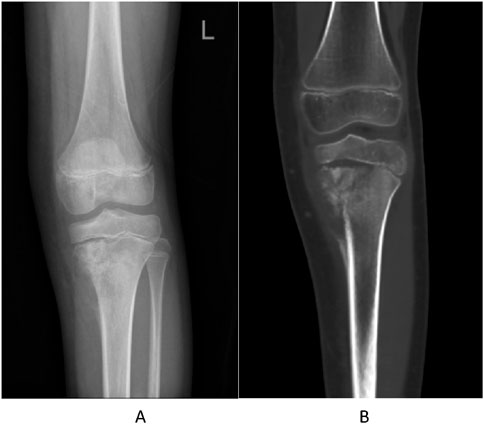

A 10-year-old girl presented with left knee pain. Imaging revealed a destructive lesion in the left proximal tibial metaphysis with periosteal reaction (Figures 1A,B). Biopsy confirmed osteoblastic osteosarcoma. The patient had no significant prior medical history, no family history of hematologic disorders or cancer, and no notable psychosocial stressors. Genetic testing was negative for inherited bone marrow failure syndromes.

Figure 1. Pre-treatment imaging of the left proximal tibia. (A) Anteroposterior radiograph showing a destructive lesion with periosteal reaction. (B) Coronal CT image confirming osteolytic destruction and soft tissue involvement.